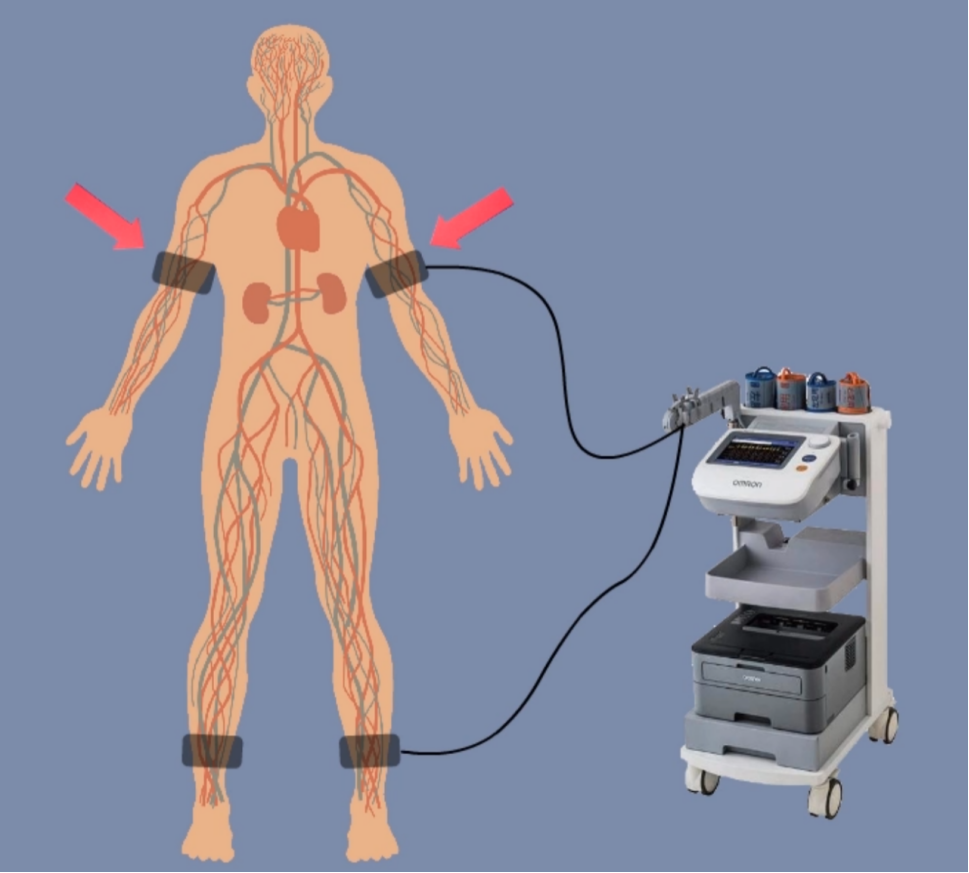

前边我们提到,脉搏波的速度、波形等信息,依赖于血管和血液的力学性质。那一个很自然的想法是,脉搏波的性质,岂不是可以很好地反映人体的健康情况!是这样!心脑血管疾病作为人类头号杀手(远超癌症),给人类健康造成了极大威胁。而脉搏波一定程度上可以反映血管的健康信息[2],比如:

通过测量不同位置的脉搏波压力变化图,可以反映血管的健康状况 | 图自[8]